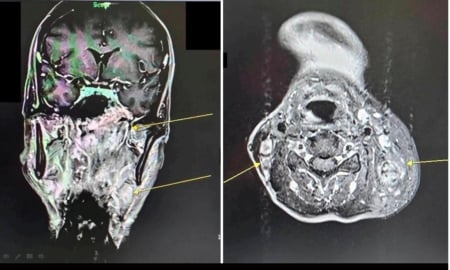

After being referred to Dajian General Hospital in Miaoli City for an MRI scan, he was diagnosed with the rare cancer which affects the area behind the nose and above the back of the throat.

Source: LTN